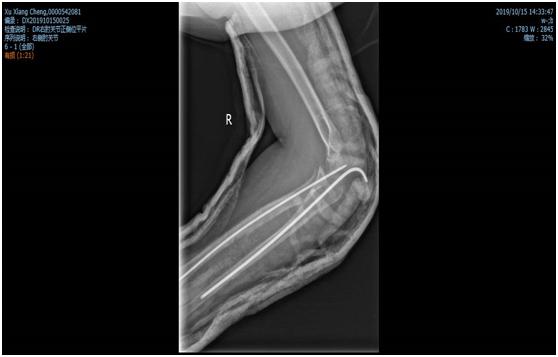

锁骨干骨折术前照片

锁骨干骨折术后照片